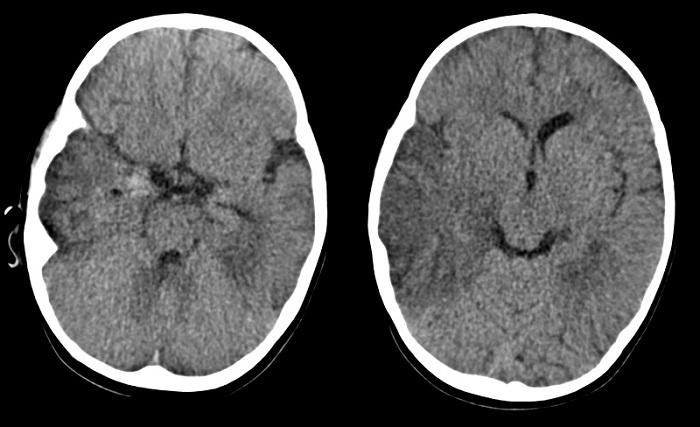

Inicialmente la paciente recibe tratamiento antibiótico intravenoso con cefuroxima ante la sospecha de discitis, que se descarta a las 48 horas del ingreso mediante gammagrafía ósea en la que no se objetivan alteraciones de significación patológica. Posteriormente ante la sospecha clínica de meningoencefalitis con persistencia de fiebre, somnolencia e irritabilidad, se inicia tratamiento antibiótico empírico con cefotaxima, vancomicina y aciclovir intravenosos. Se realiza tomografía computarizada (TC) craneal en el que se observan hipodensidades en las áreas parietotemporal derecha y temporal izquierda, con discreto efecto de masa, con pequeños focos hiperdensos sugestivos de hemorragia en punta del temporal derecho (Fig. 1). Dichos hallazgos sugieren una posible encefalitis herpética. Tras la TC craneal se decide realizar punción lumbar con los siguientes resultados en el líquido cefalorraquídeo (LCR): hematíes 3500/mm3, células nucleadas 150/mm3 (segmentados: 1%, linfocitos: 82%, células mononucleares: 17%), glucorraquia 0,40 g/l y proteinorraquia 1,01 g/l.